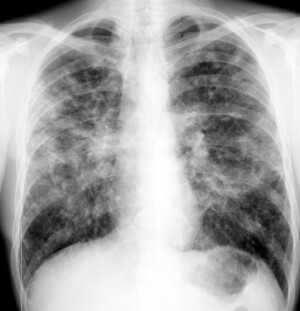

Диссеминированное туберкулезное заболевание легких. Заболевание появляется как последствие широкого гематогенного расширения туберкулезной инфекции. Началом недуга, в основном, есть лихорадка фебрильная, после неё быстро проявляется интоксикация. Человек страдает наличием сухого кашля и одышки. Анализ туберкулеза в легких осуществляется способом рентгенографии. Одновременно, анализ мокроты не дает результатов по причине отсутствия в ней микобактерий. Ещё о диагнозе свидетельствует биопсия трансбронхиальная. Осложнениями такого состояния способны стать сердечно-легочный недостаток, анемия, отсевы гематогенные в различные органы и пр.

При рентген-исследовании выявляются воспалительные поражения легких, очаги некроза и рубцовые изменения.

- На рентген-пленке можно обнаружить признаки поражения легких в активной стадии и рубцовые изменения после излечения, а также участки кальцификации в грудных лимфоузлах.